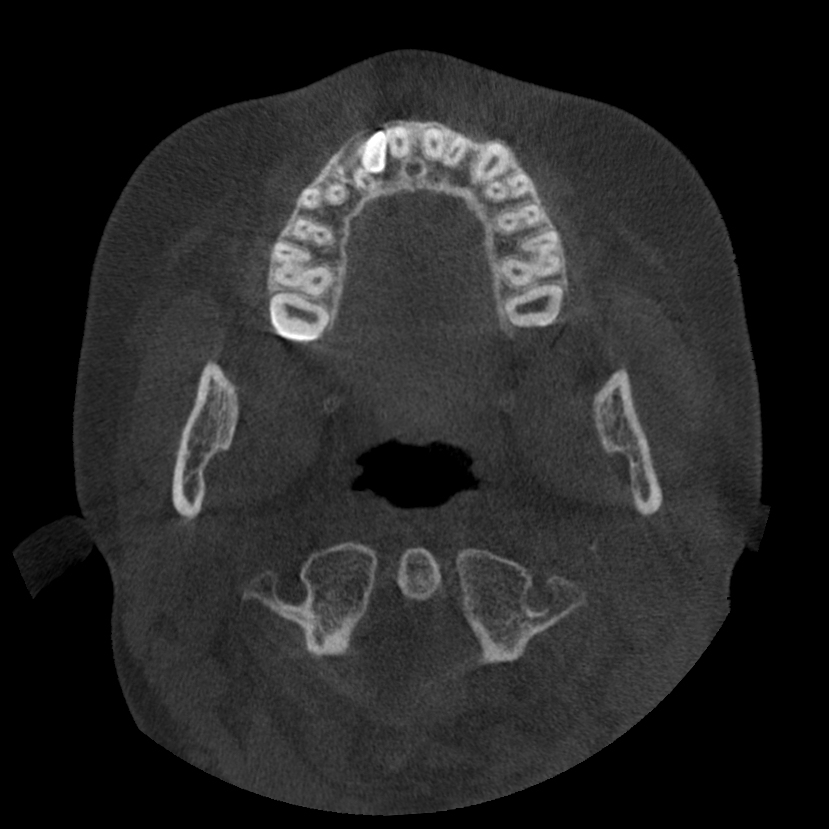

La Tomografia Computerizzata Cone Beam è stata adottata nel nostro studio per l'imaging diagnostico 3D nel 2010.

Non viene utilizzata di routine ma solo in casi complessi seguendo sempre il principio ALARA (As Low As Reasonably Achievable=Esposizione alle radiazioni X il più basso possibile in accordo alle esigenze diagnostiche e terapeutiche).